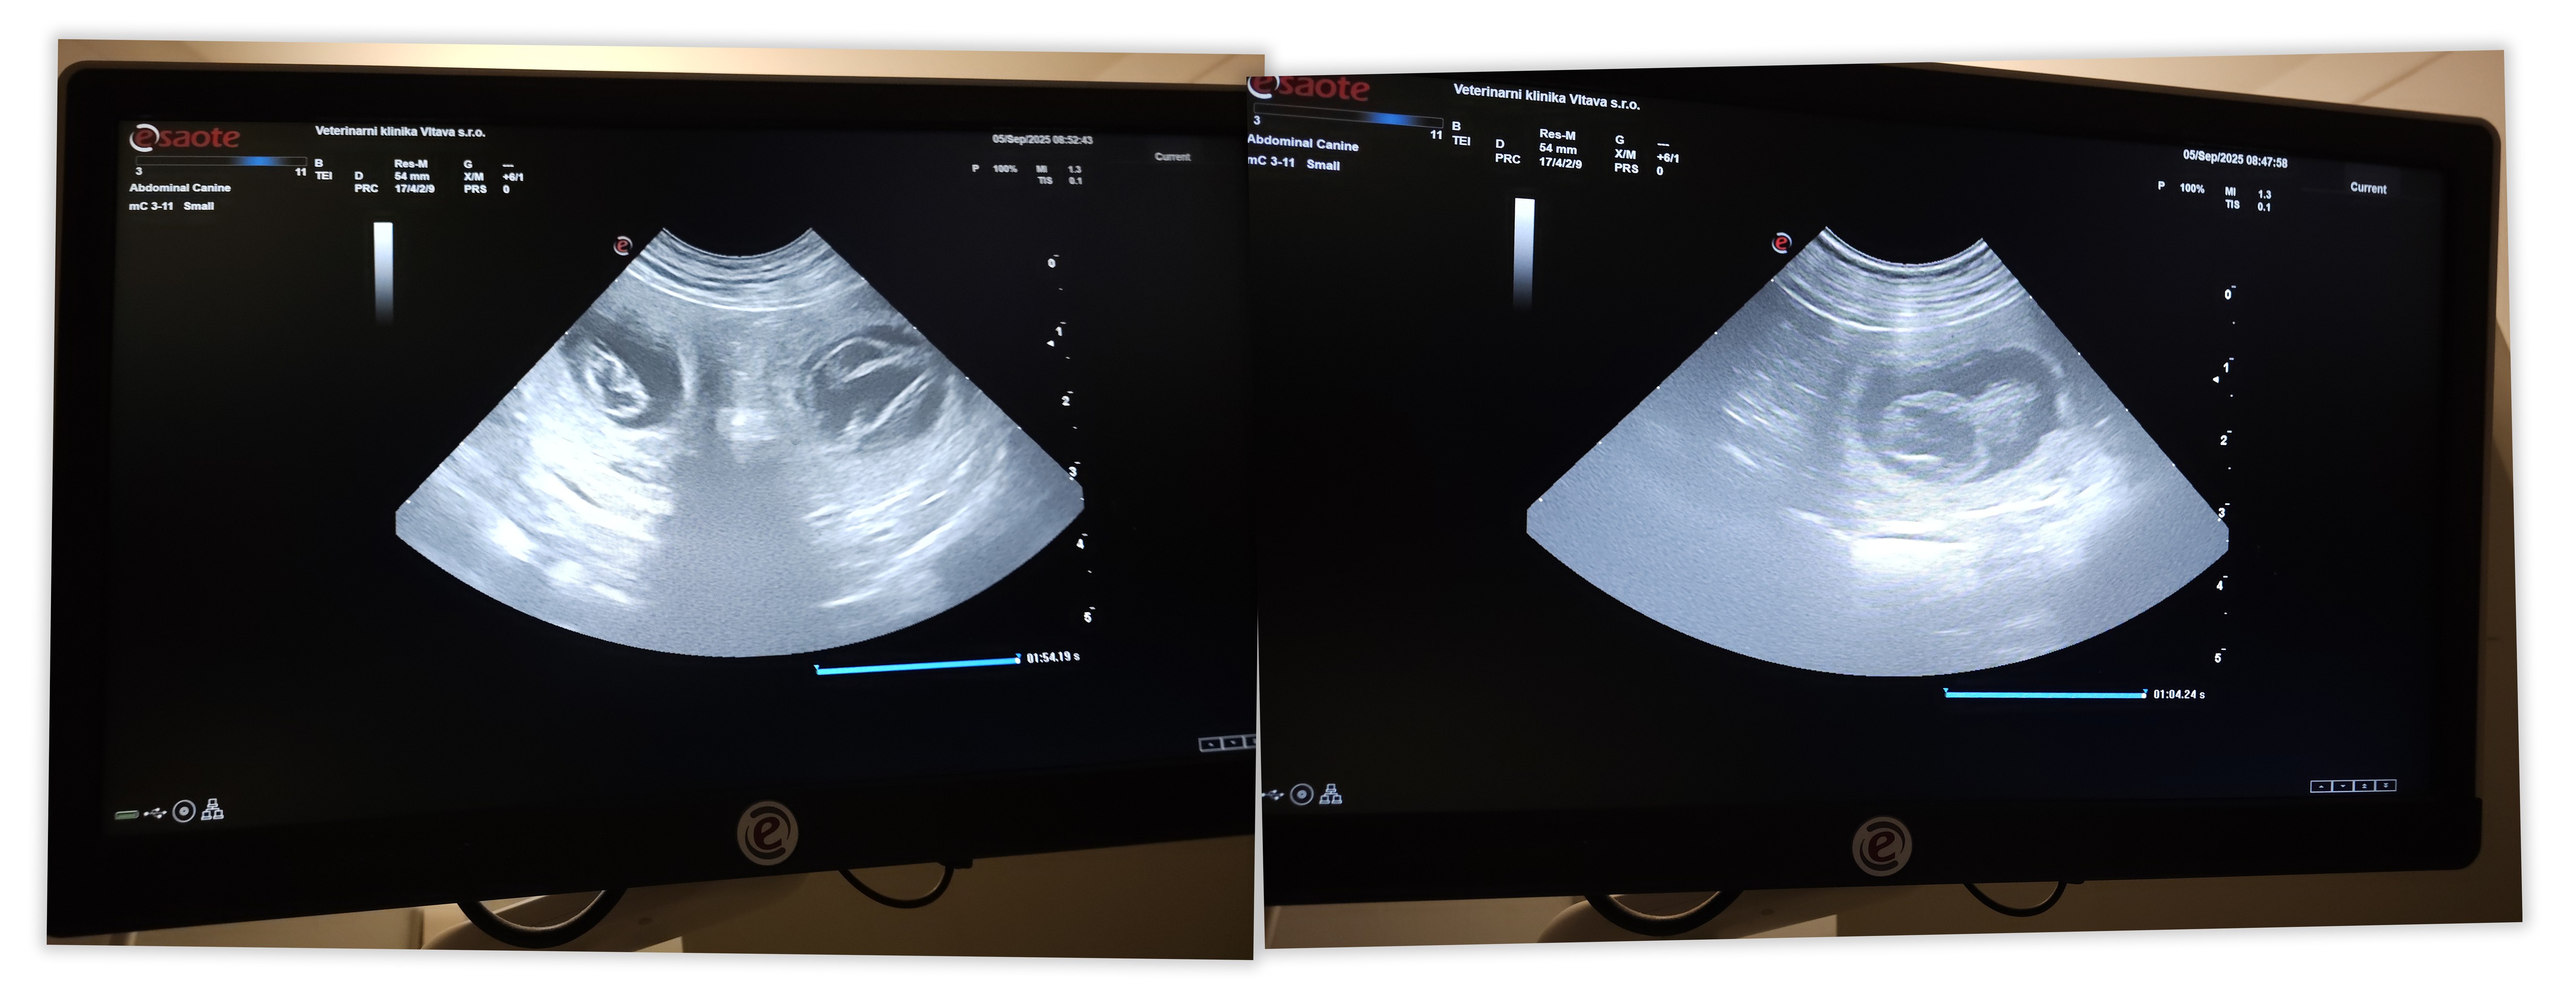

06.09.2025 - Dnešní ranní sonografie potvrdila, co jsme si tolik přáli - Abynka je březí!

S paní veterinářkou jsme objevili minimálně 6 kuliček v bříšku, lze tedy předpokládat početný vrh. Určitě mezi nimi bude schovaná i mladší sestřička Larušky ![]()